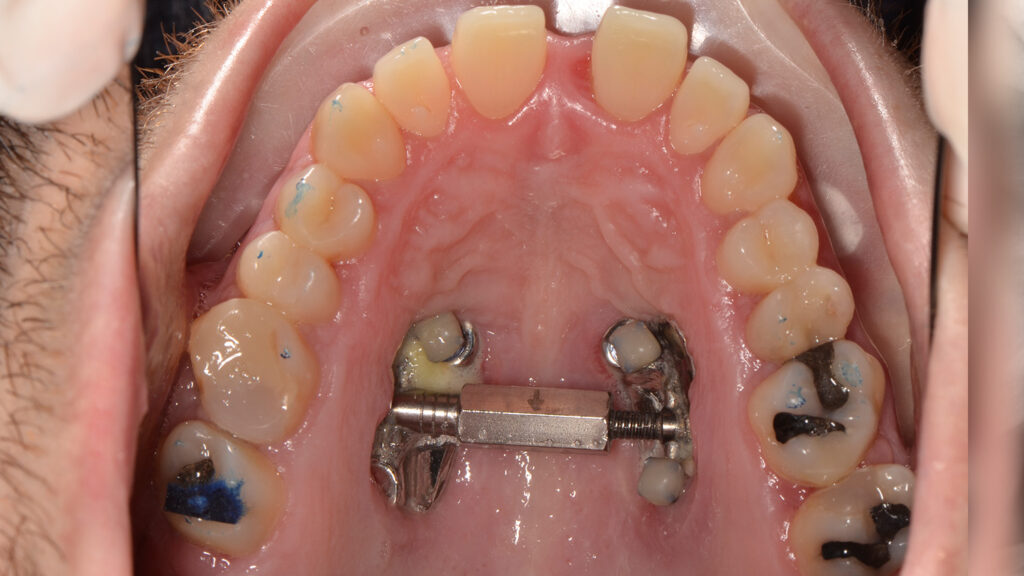

The patient was informed of various treatment options, including combined orthognathic surgery and orthodontic appliances. However, he opted against surgery. Consequently, a compensatory orthodontic treatment plan using MARPE (Mini-Implant Assisted Rapid Palatal Expander) and Spark Aligners was chosen, after the extraction of the existing third molars and treatment of the cavities.

The primary goal of the treatment was to correct the transverse deficiency of the maxillary arch (>5 mm) and resolve the skeletal crossbite. MARPE was used to address this transverse issue.

Once the transverse discrepancy was corrected, treatment continued with Spark Aligners to address the vertical plane. The planned vertical correction involved extruding the upper anterior teeth, with 1.7 mm of extrusion in the upper arch, and 1.5 mm in the lower arch using attachments. To assist in bite closure, turbo bites were employed to intrude the mandibular molars.